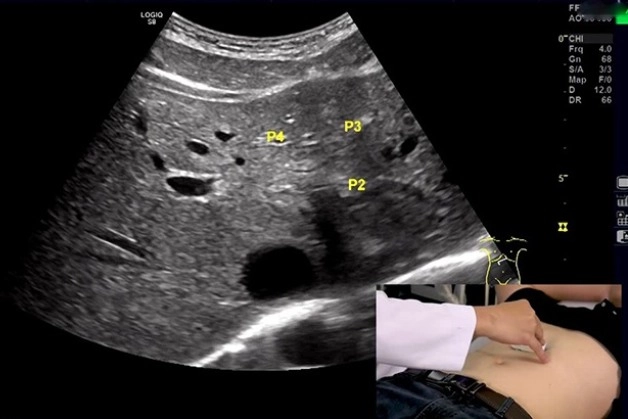

Siêu âm là một kỹ thuật chẩn đoán quen thuộc, không xâm lấn và an toàn với người bệnh. Siêu âm ruột thừa là kỹ thuật hỗ trợ hiệu quả trong chẩn đoán và quan sát tình trạng ruột thừa với độ chính xác lên rất cao (trên 90%).

Các bác sĩ sử dụng kỹ thuật đầu dò với tần số cao rồi đè ép đầu dò tới vùng bụng bị đau để khảo sát và đánh giá sự sưng tấy của ruột thừa. Từ đó có thể dễ dàng đưa ra kết luận về tình trạng bệnh tại ruột thừa.

Siêu âm tại ruột thừa là kỹ thuật hỗ trợ hiệu quả trong chẩn đoán và quan sát tình trạng ruột thừa với độ chính xác cao